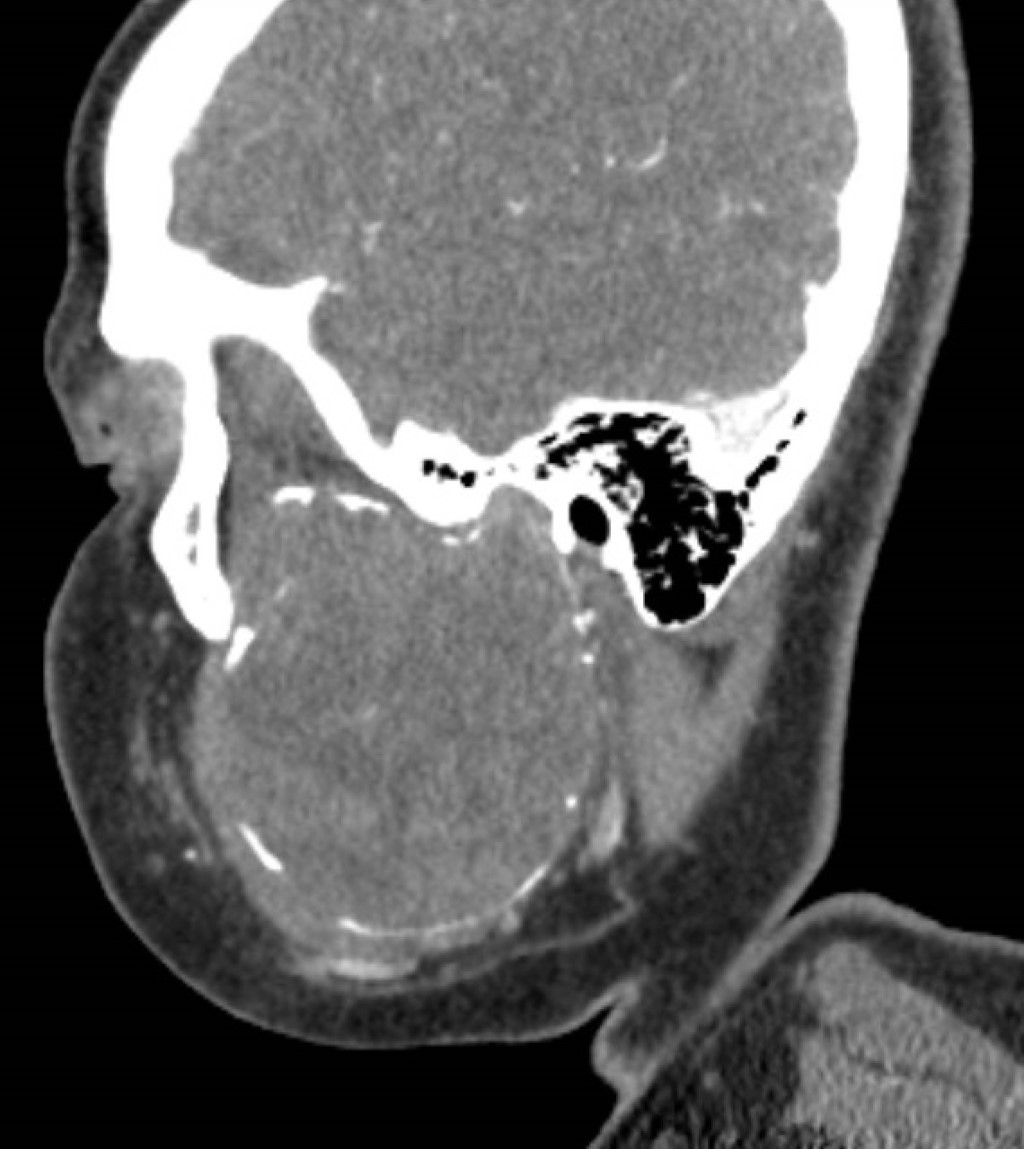

La tomografía contrastada mostró una lesión osteolítica bien delimitada con bordes escleróticos, afectando cóndilo, rama y cuerpo mandibular izquierdo posterior al primer premolar; la lesión medía 56 × 70 × 66 mm, con erosión del maxilar izquierdo y desplazamiento de arteria carótida externa y vena yugular interna (Figuras 2, 3, 4, 5 y 6).

Figura 2

Figura 3

Figura 4

Figura 5

Figura 6